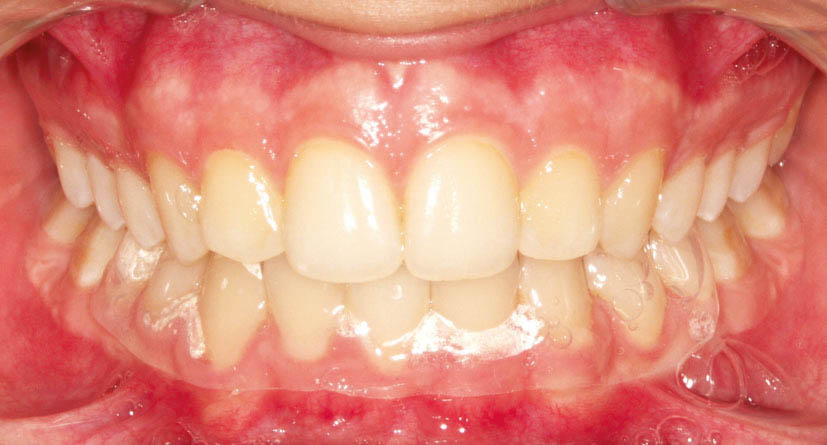

شکل 115-2: نتیجه درمان همان 2mm کلاسII تمام میشود.

وقتی 2mm کلاسII باشد (شکل 114-2) اگر پرمولرهای بالا را فقط بخاطر 2mm کلاسII بودن بکشید آن موقع برای رسیدن به یک کاسپ کامل کلاسII، مولرهای شما باید 5mm حرکت مزیالی بکنند که از لحاظ مکانیکی کاری بسیار سخت است. بیماران هم شکایتی از اورجت زیاد ندارند چون 2mm کلاسII اورجت زیادی برای آنها درست نمیکند. این بیماران را مانند بیماران کلاسI (منتهی حد مزیالی آن) قبول میکنیم و چون بنا برغیرکشیدنی بودن فک پائین است، لذا بالا را هم غیرکشیدنی درنظر میگیریم و ارتودنسی را تمام میکنیم (شکل 115-2).